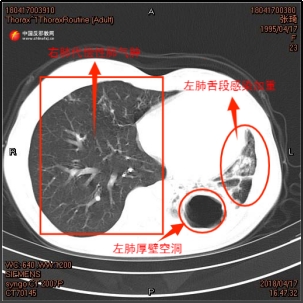

Bei der zweiten Tuberkulose-Diagnose im April 2018 bestätigte eine Sputumkultur von Zhang Qi eine begleitende Aspergillus-Infektion. Der damalige Stationsarzt Zhang Yang erinnerte sich an die Behandlungsschwierigkeiten: „Bei Zhang Qi wurde zum zweiten Mal eine rezidive, resistente Tuberkulose diagnostiziert. Wir erstellten einen gezielten Behandlungsplan und fügten orale Antimykotika hinzu.“ Die während der Behandlung mehrfach angefertigten CT-Aufnahmen des Brustkorbs von Zhang Qi dokumentierten ebenfalls die Verschlechterung ihrer linken Lunge. Die Höhle im linken Unterlappen von Zhang Qi vergrößerte sich allmählich, der Lungenlappen atrophierte, und die Infektion verstärkte sich zunehmend.

▲ links: CT-Aufnahme von Zhang Qis Brustkorb vom April 2017;

rechts: CT-Aufnahme von Zhang Qis Brustkorb vom April 2018